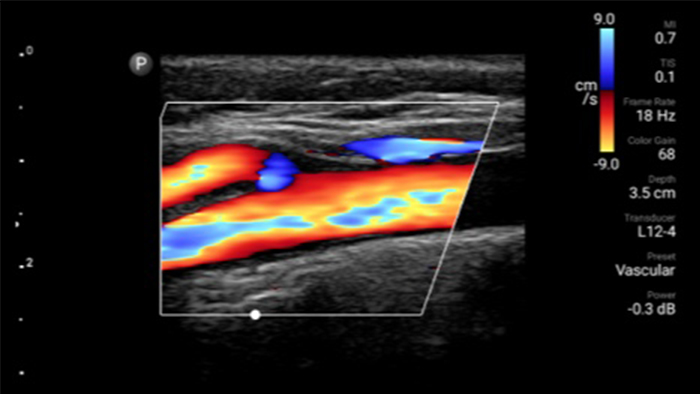

Reduzca las complicaciones en procedimientos guiados por aguja

El ultrasonido portátil Lumify para anestesiología le ayuda a visualizar claramente la definición de los bordes con la colocación de la aguja, los nervios circundantes, los vasos sanguíneos y los planos fasciales.